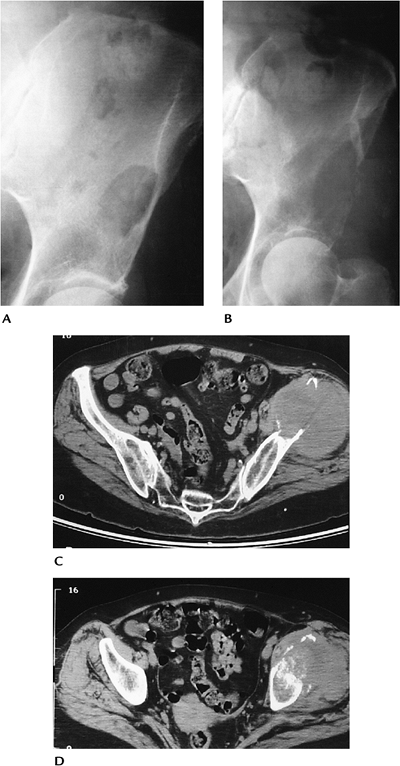

FIGURE 10-34 Malignant fibrous histiocytoma. Routine radiographs showing a lytic lesion in the left ileum (A) that 11 months later (B) has increased dramatically and fractured laterally. (C,D) Axial CT images showing bone destruction and large soft tissue mass with osseous sequestra.